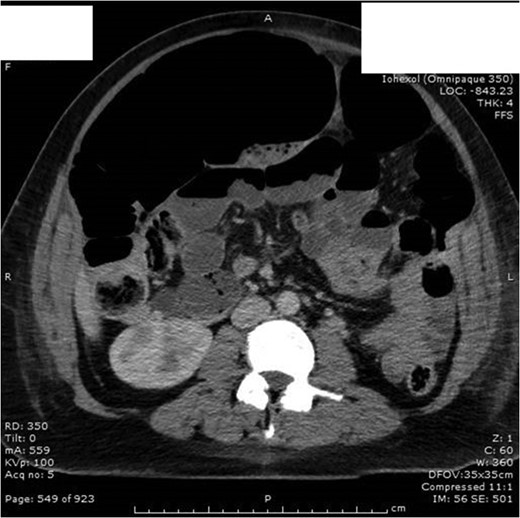

On Day 1 post surgery she was noted to be tachycardic, febrile and hypertensive with a drop in saturation 92–93% on room air along with abdominal pain. Her differential diagnosis included atelactesis, pulmonary embolism and endometriosis (Fig. 1). On examination she had good bowel sounds, was passing flatus but had not opened her bowels. On Day 2 she had localized right lower quadrant tenderness with raised inflammatory markers of CRP 163, WCC 21 × 109/l and neutrophil count 17 × 109/l. The computed tomography (CT) scan of her abdomen/pelvis (A/P) showed evidence of ileus with dilated loops of bowel (Fig. 2).

Day 2 post op CT A/P with no evidence of intra-abdominal collection/foreign body. Dilatation of entire intestine (large bowel up to 9 cm) most likely representing postsurgical ileus rather than a mechanical obstruction.